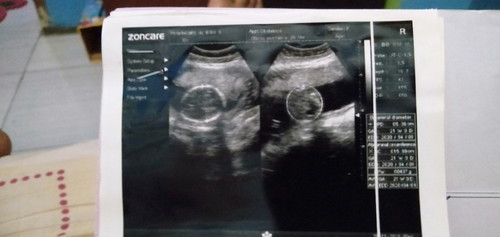

Untuk adikku trimakasih kalian udah menjadi adik yang baik dari awal tth hamil sampe sekarang kalian slalu jagain tth . Slalu membawa sesuatu berupa makanan kalo pulang sekolah . Slalu doain de utun klo pulang ngaji . Alhamdulillah adik adik ku soleh dua dua nya . Trimakasihh banyakk untukk kasih sayang nya ,, om om kecilku Wildan Nuryana dan Ridwan Syaiful Syawal #terimakasihkuharike3